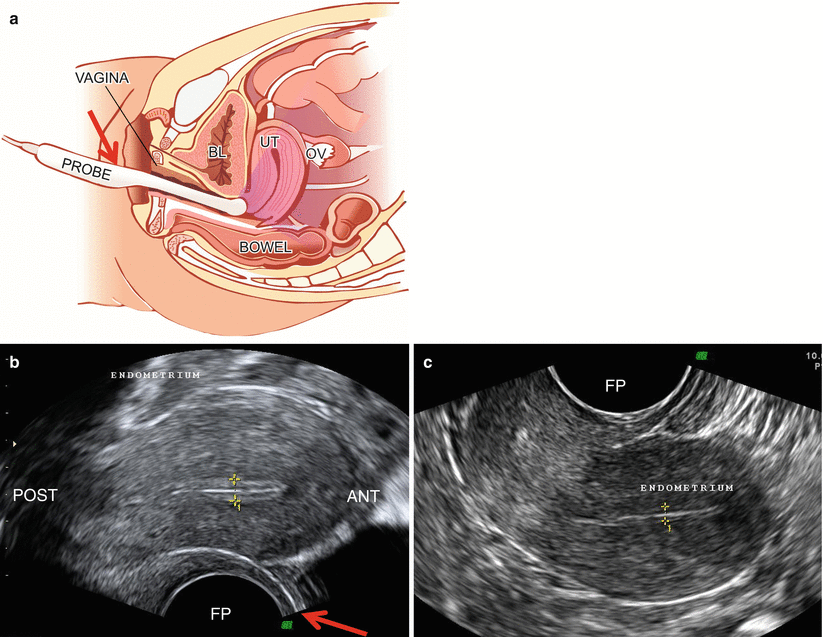

From obgynkey.com

General Techniques in Gynecological Ultrasound Obgyn Key What Does Probe Mean In The Army Find out the origin, usage and. Get the most popular probe abbreviation related to military. What does probe stand for in military? Your abbreviation search returned 10 meanings. What does probe stand for? Learn the meaning of military jargon and expressions used by service members in the armed forces. Find standard us military and associated terminology, including abbreviations, acronyms, and. What Does Probe Mean In The Army.